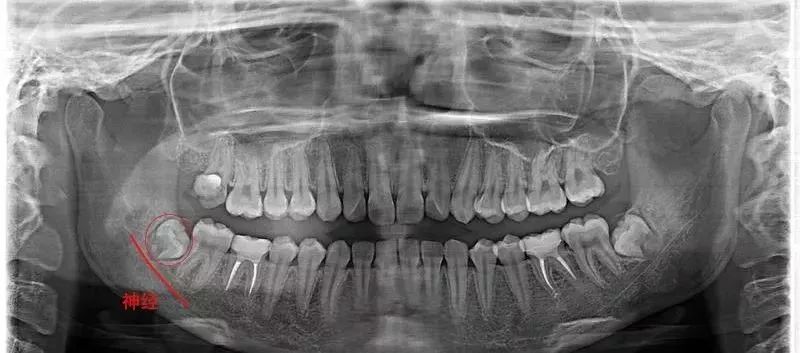

智齿刚萌出时的牙周膜时牙周膜对智齿“抓”得还没那么牢固,再加上周围骨质较松,拔牙时骨阻力较少。欣赏一下整齐的、牙根尚未发育完全的智齿↓

医生拔得轻松,你也恢复得更快。18岁的牙根 vs 28岁的牙根↓